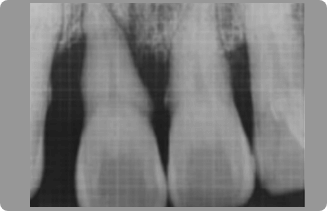

歯は骨と歯根膜(しこんまく)というごく薄い組織によって連結しています。硬い物を強く噛むと、この組織が一過性の炎症を起こします。

つまり足首を捻挫したのとおなじ状態になるのです。歯が捻挫した時は湿布は貼れませんが、できるだけ物を噛まないように安静にしていたら、1週間以内には治るでしょう。

それ以上痛みが長く続くようでしたら、歯周病の悪化、歯根の病気、歯根の破折も疑われます。早めに歯科を受診しましょう。